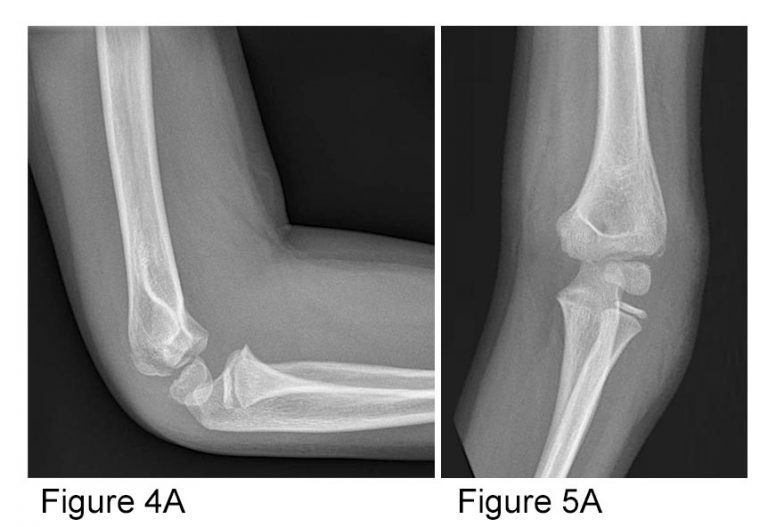

Xray Elbow Showing Fracture Proximal Ulna or Olecranon Fracture How To Fix Elbow Fracture In most olecranon fractures, however, the pieces of bone move out of place when. treatment may be as simple as elevating the splinted arm, applying ice to swollen areas, and taking pain relievers. treatment depends on the type of elbow fracture you have and the severity of your condition. simple fractures can be treated with a brief. How To Fix Elbow Fracture.

Xray Elbow Showing Supracondylar Humerus Fracture and Post Opretion How To Fix Elbow Fracture During this surgical procedure, the bones are. nonsurgical treatment options usually involve: simple fractures can be treated with a brief period of immobilization with a splint or sling followed by moving the elbow to pain tolerance. Immobilization of the elbow using a cast, brace, or sling. if the fracture is severe, your surgeon may recommend an open. How To Fix Elbow Fracture.